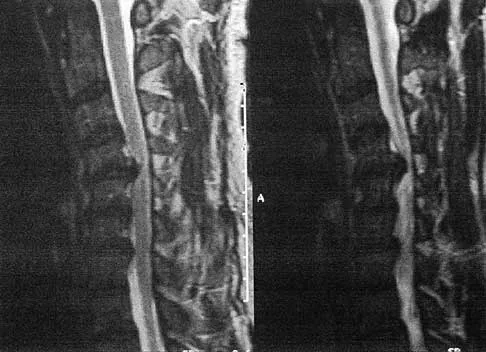

A patient who has had neck pain radiating down the arm for the past 4 weeks reports that the pain was excruciating during the first week. Management consisting of anti-inflammatory drugs and physical therapy has decreased the neck and arm symptoms from 10/10 to 3/10. He remains neurologically intact. MRI and CT scans are shown in Figures 5a and 5b. The best course of action should be

Explanation

Although the patient has a large herniated nucleus pulposus, the pain has decreased from 10/10 to 3/10 over a 4-week period and the patient is now free of any neurologic symptoms. It is quite likely that further nonsurgical management will continue to resolve his symptoms. In the absence of any neurologic deficits, there is no evidence that the patient is at significant risk for paralysis. Saal JS, Saal JA, Yurth EF: Nonoperative management of herniated cervical intervertebral disc with radiculopathy. Spine 1996;21:1877-1883.